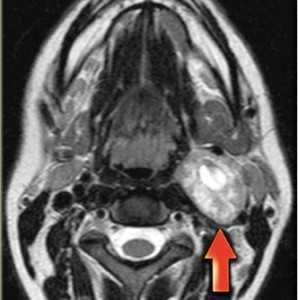

(Слева) МРТ Т1ВИ FS с КУ, аксиальная проекция. В задних отделах подподъязычного сонного пространства расположено образование округлой формы. Шваннома симпатического ствола смещает и сонную артерию, и внутреннюю яремную вену кпереди. Одновременное смещение обоих сосудов сонного пространства весьма характерно для шванномы симпатического ствола.

(Справа) МРТ Т1ВИ FS c КУ, коронарная проекция. Шваннома симпатического ствола, расположенная в сонном пространстве. Опухоль неравномерно накапливает контрастное вещество. Участки кистозного перерождения в крупных шванномах встречаются достаточно часто.